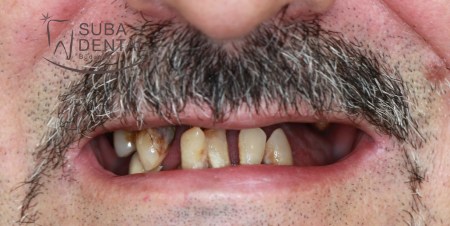

Before